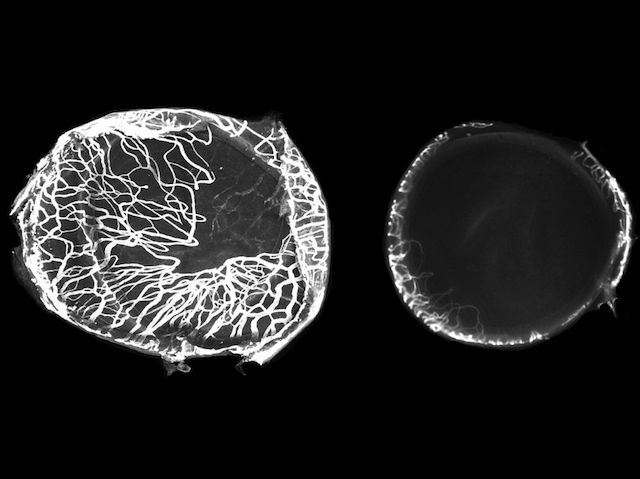

Birthmarks come in all shapes and sizes but they don’t all last forever. Take infantile hemangiomas, also known as strawberry marks. These are tumours made of tangled blood vessels beneath the skin. Occasionally they need to be treated with the drug propranolol. Researchers now demonstrate that propranolol also successfully treats some of the symptoms of a rare syndrome called HLTRS in which abnormal blood vessel growth can affect many organs and is caused by a mutation in the SOX18 gene. Using a mouse model of HLTRS, the team found that propranolol resolved the abnormal blood vessel growth in the cornea, as revealed by fluorescence microscopy of treated (pictured, right) and untreated eyes (left). Further tests showed a specific form of the drug, R-propranolol, acts specifically to reduce SOX18 activity. These insights highlight the importance of SOX18 in blood vessel tumours and the potential for R-propranolol in treating these and other vascular diseases.